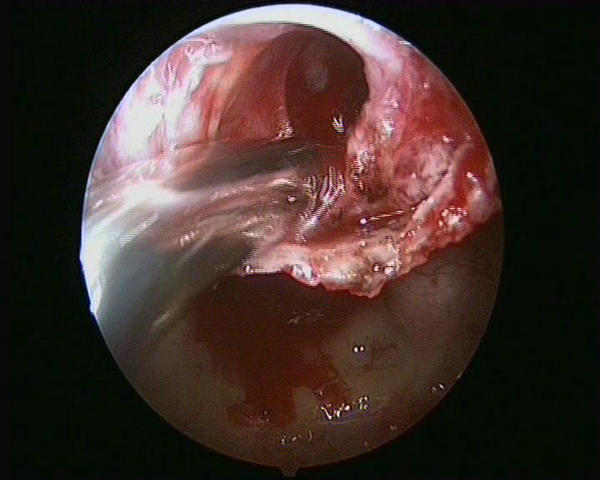

近两个多月来,患者王女士感到右眼视力明显下降,伴有头痛,起初她以为是近视加深,没想到到郑州大学五附院检查,头部磁共振在她的脑袋里找到一颗红枣大小的脑垂体瘤(图1)。

图1